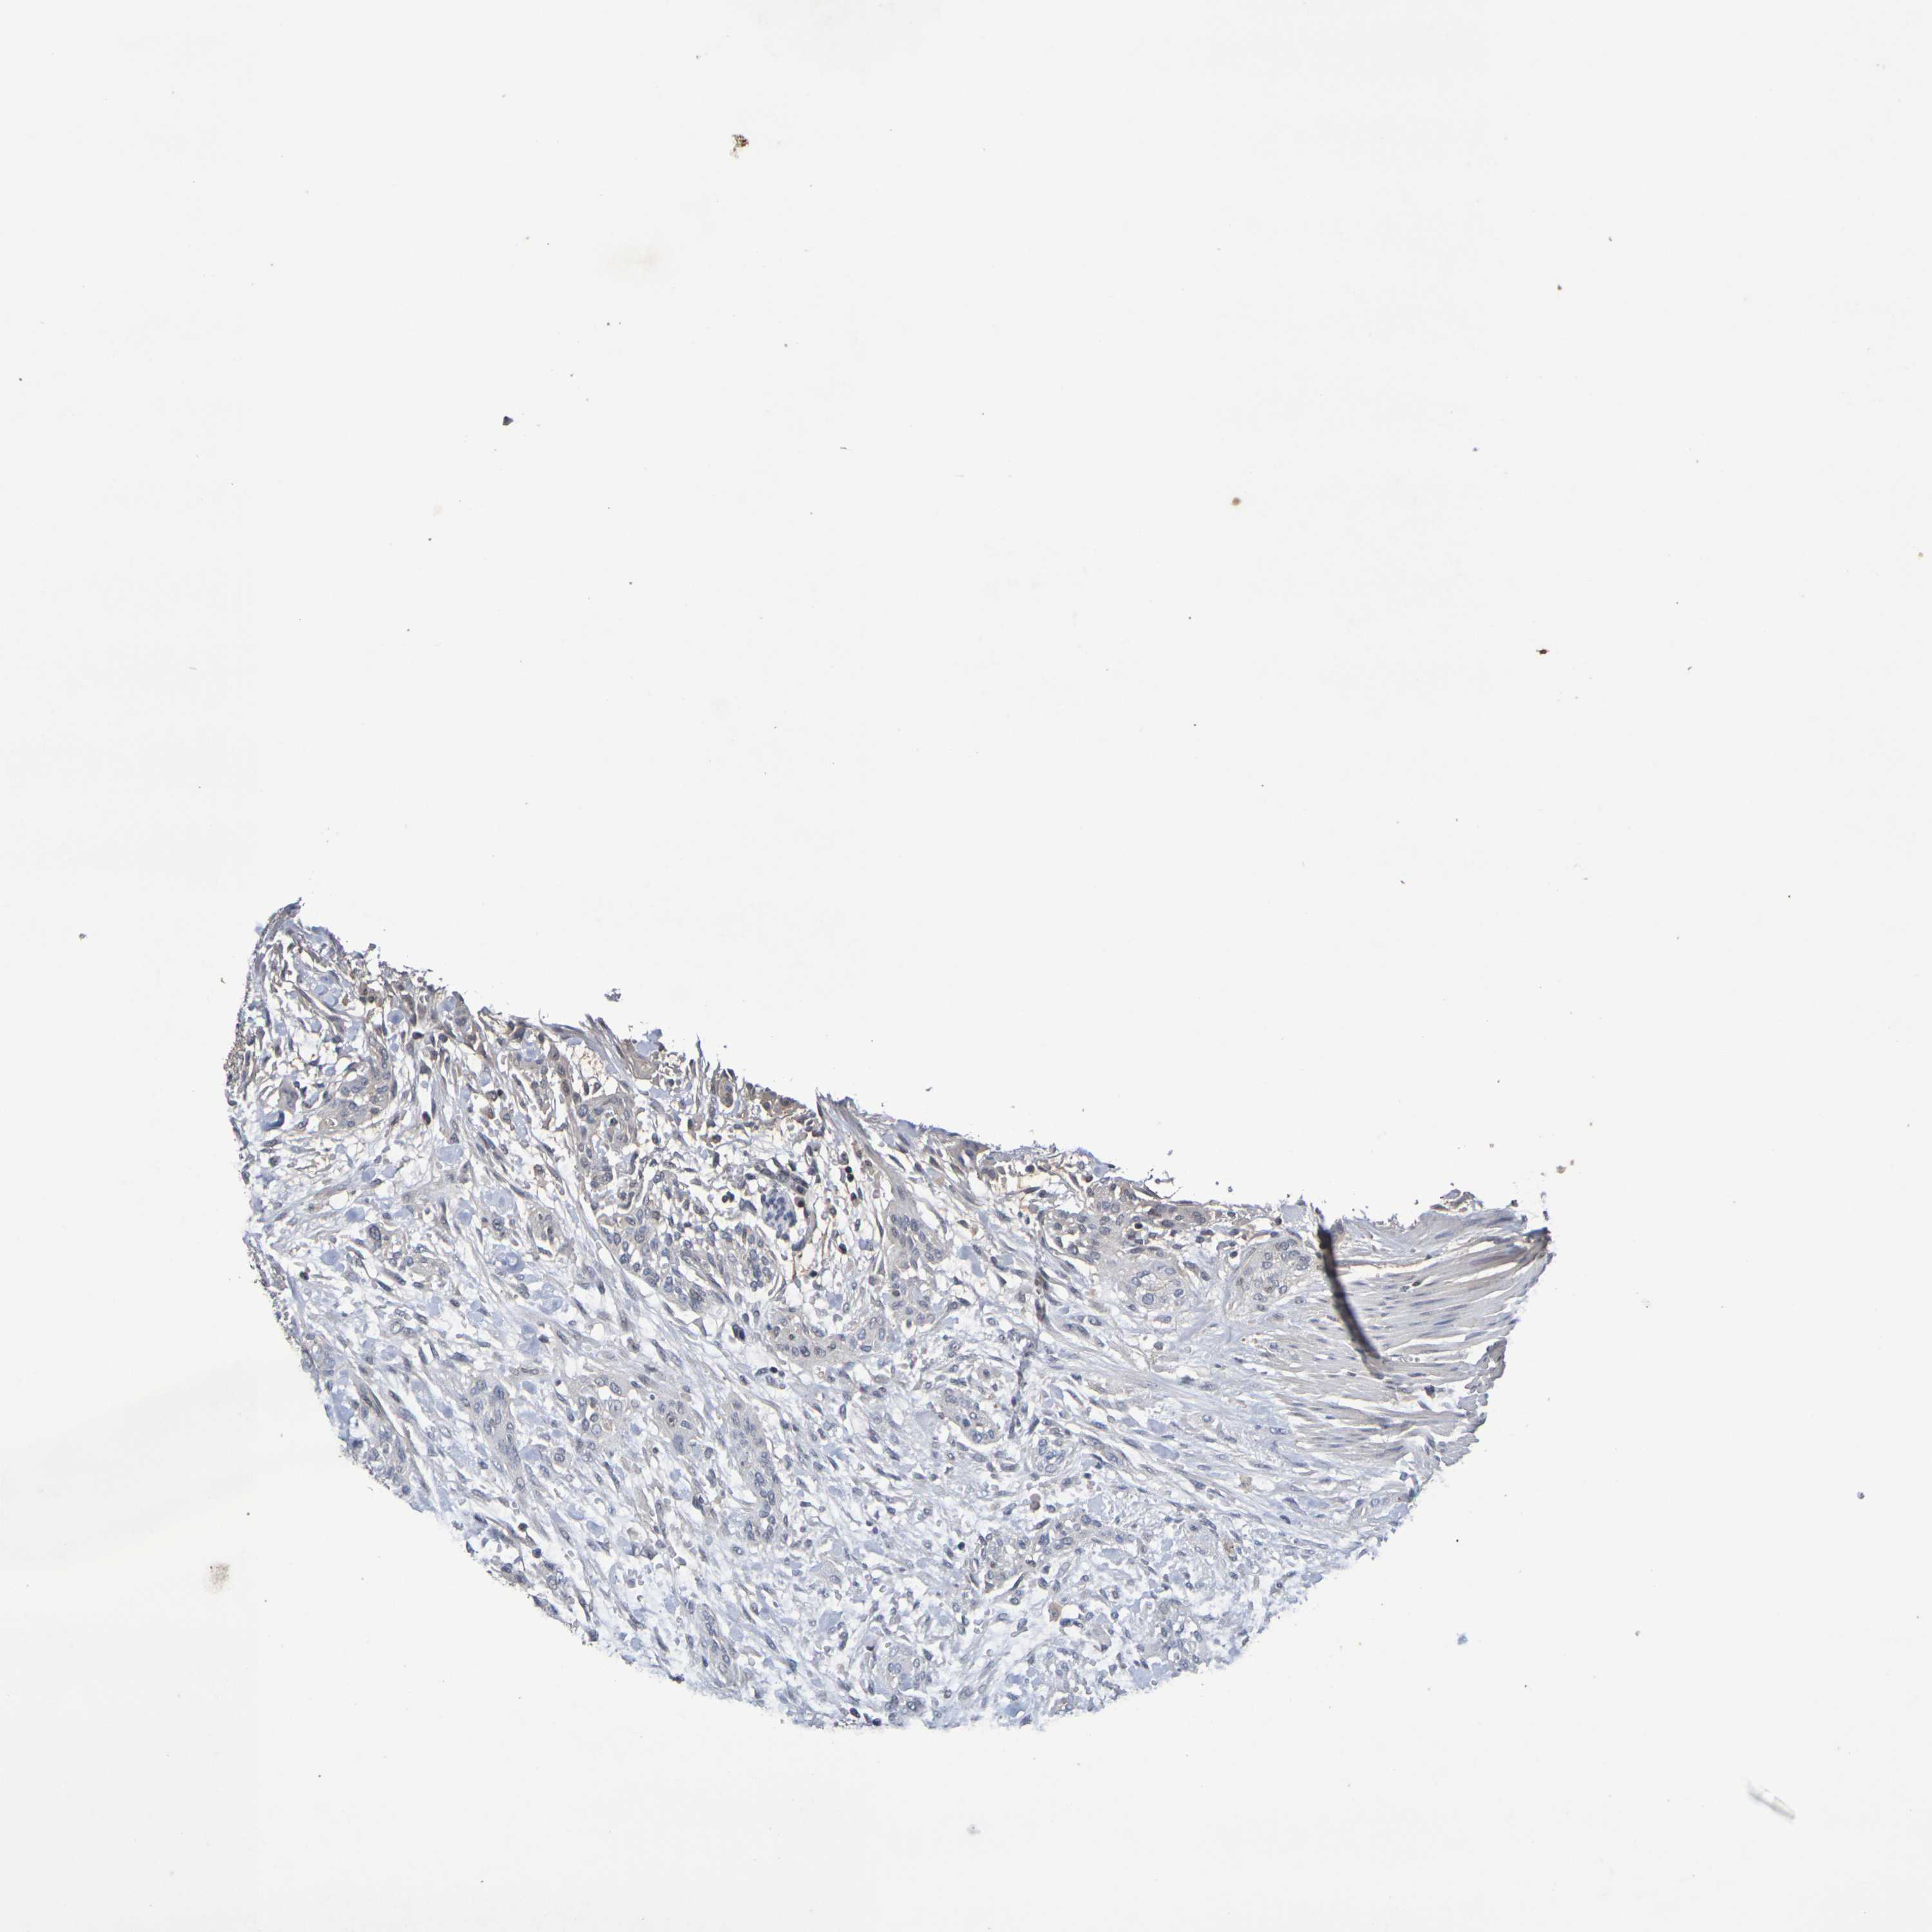

UROTHELIAL CANCER - Protein expressioni

A mouse-over function shows sample information and annotation data. Click on an image to view it in a full screen mode. Samples can be filtered based on level of antibody staining by selecting one or several of the following categories: high, medium, low and not detected. The assay and annotation is described here.

Note that samples used for immunohistochemistry by the Human Protein Atlas do not correspond to samples in the TCGA dataset.

Antibody stainingi

Antibody staining in the annotated cell types in the current human tissue is reported as not detected, low, medium, or high, based on conventional immunohistochemistry profiling in selected tissues. This score is based on the combination of the staining intensity and fraction of stained cells.

Each image is clickable and will lead to virtual microscopy that enables deeper exploration of all samples and also displays staining intensity scores, fraction scores and subcellular localization as well as patient and tissue information for each sample.

Antibody HPA001907

Antibody HPA002735

Antibody CAB010451

Antibody CAB080271

Urothelial carcinoma, High grade

Urothelial carcinoma, Low grade